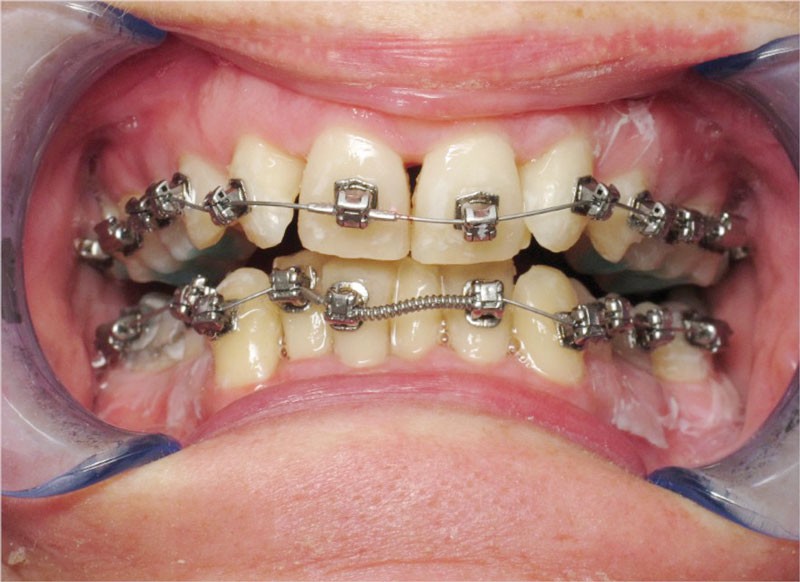

Un appareillage Damon métal a été mis en place, réalisé à partir d’un set up numérique Insignia pour obtenir un contrôle précis des torques et de la forme d’arcade et réduire le temps de finition grâce à un collage indirect très précis.

De larges surélévations postérieures étalées ont été mises en place et la patiente a porté des élastiques précoces suivant les principes de la technique Damon. Les 14 et 24 rempliront le rôle des 13 et 23.

L’objectif, en utilisant la technique Insignia est de réduire le temps de traitement de 28 à 18 mois avec 12 rendez-vous (fig. 5 à 14).